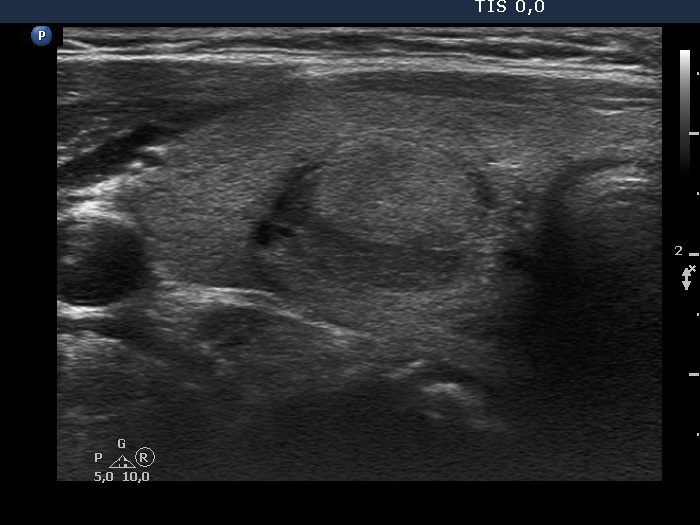

Comment. The judgement of several ultrasound characteristics is not easy in this case. First, the echogenicity of the nodule: echonormal and hypoechoic parts occur in roughly equally. The borders present undulation at the ventral and lower parts which can be regarded pathological. Finally, the intranodular echogenic figures are also difficult to judge.